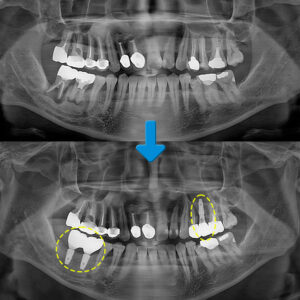

환 자분께서는 오른쪽 위아래의 어금니가 잇몸이 많이 붓고 무언가 저작할 때마다 아픔과 함께 심어논 치아가 흔들린다는 주소로 내원해 주셨는데요. 파노라마 사진을 보시면 오른쪽 위아래의 어금니 치아에 염증성 소견이 발견되었습니다.

이 환 자분의 경우 전반적으로 치주염이 존재하였습니다. 오른쪽 아래 두 번째 큰 어금니의 뿌리 주변으로 검은색 투과성의 염증이 보이며, 특히 오른쪽 위에 심어놓은 어금니 주변으로는 분화구 모양으로 잇몸뼈가 흡수된 양상을 보였는데요.

또한 오른쪽 위의 어금니 부위에는 광대뼈 안쪽이 공간인 상악동이 위치하고 있는데요. 임플란트 주위염으로 인해 잇몸뼈의 소실이 많이 진행되었고, 상악동도 아래로 많이 내려와 상악동 거상술을 동반한 재식립이 필요하였습니다.

따라서 오른쪽 위의 염증이 이미 많이 진행된 큰 어금니 2개와 오른쪽 아래의 두 번째 큰 어금니 치아는 발치를 가장 먼저 진행하고, 내부의 염증을 제거한 후, 빈 공간에 임플란트 식립을 하기로 치료 계획을 세웠습니다. 우선 발치를 진행하였고, 발치 후의 상태를 보시면 남은 잇몸뼈가 거의 없는 것을 확인할 수 있습니다.

상악동 거상술이란 안정적인 식립을 위해 상악동 막을 들어 올린 후 빈 공간에 뼈이식을 하여 식립을 위한 공간을 확보해 주는 방법입니다. 쉽게 말하면 임플란트를 심을 수 있는 뼈의 양을 확보하는 것이죠. 가정동임플란트를 추천 받고 오신 환 자분의 파노라마 사진을 보시면 오른쪽 위의 상악동 거상술과 뼈이식이 온전하게 잘 진행되어 비어있던 부분이 채워져 있는 모습을 보실 수 있습니다.

왼쪽의 상악동 거상술 전의 모습에서는 임플란트를 제거한 후의 모습으로 잇몸뼈의 양이 얼마 남지 않은 모습이며, 오른쪽은 상악동 거상술과 뼈이식을 함께 진행하여 뼈의 양이 충분하게 찬 것을 볼 수 있습니다.

상악동 거상술을 동반한 식립까지 안정적으로 마친 모습인데요. 상악동 거상술을 진행한 경우에는 현재 환 자분의 상태에 따라 뼈이식과 동시에 식립하기도 하고 단단해지기까지 기다린 후 식립을 진행하기도 합니다.